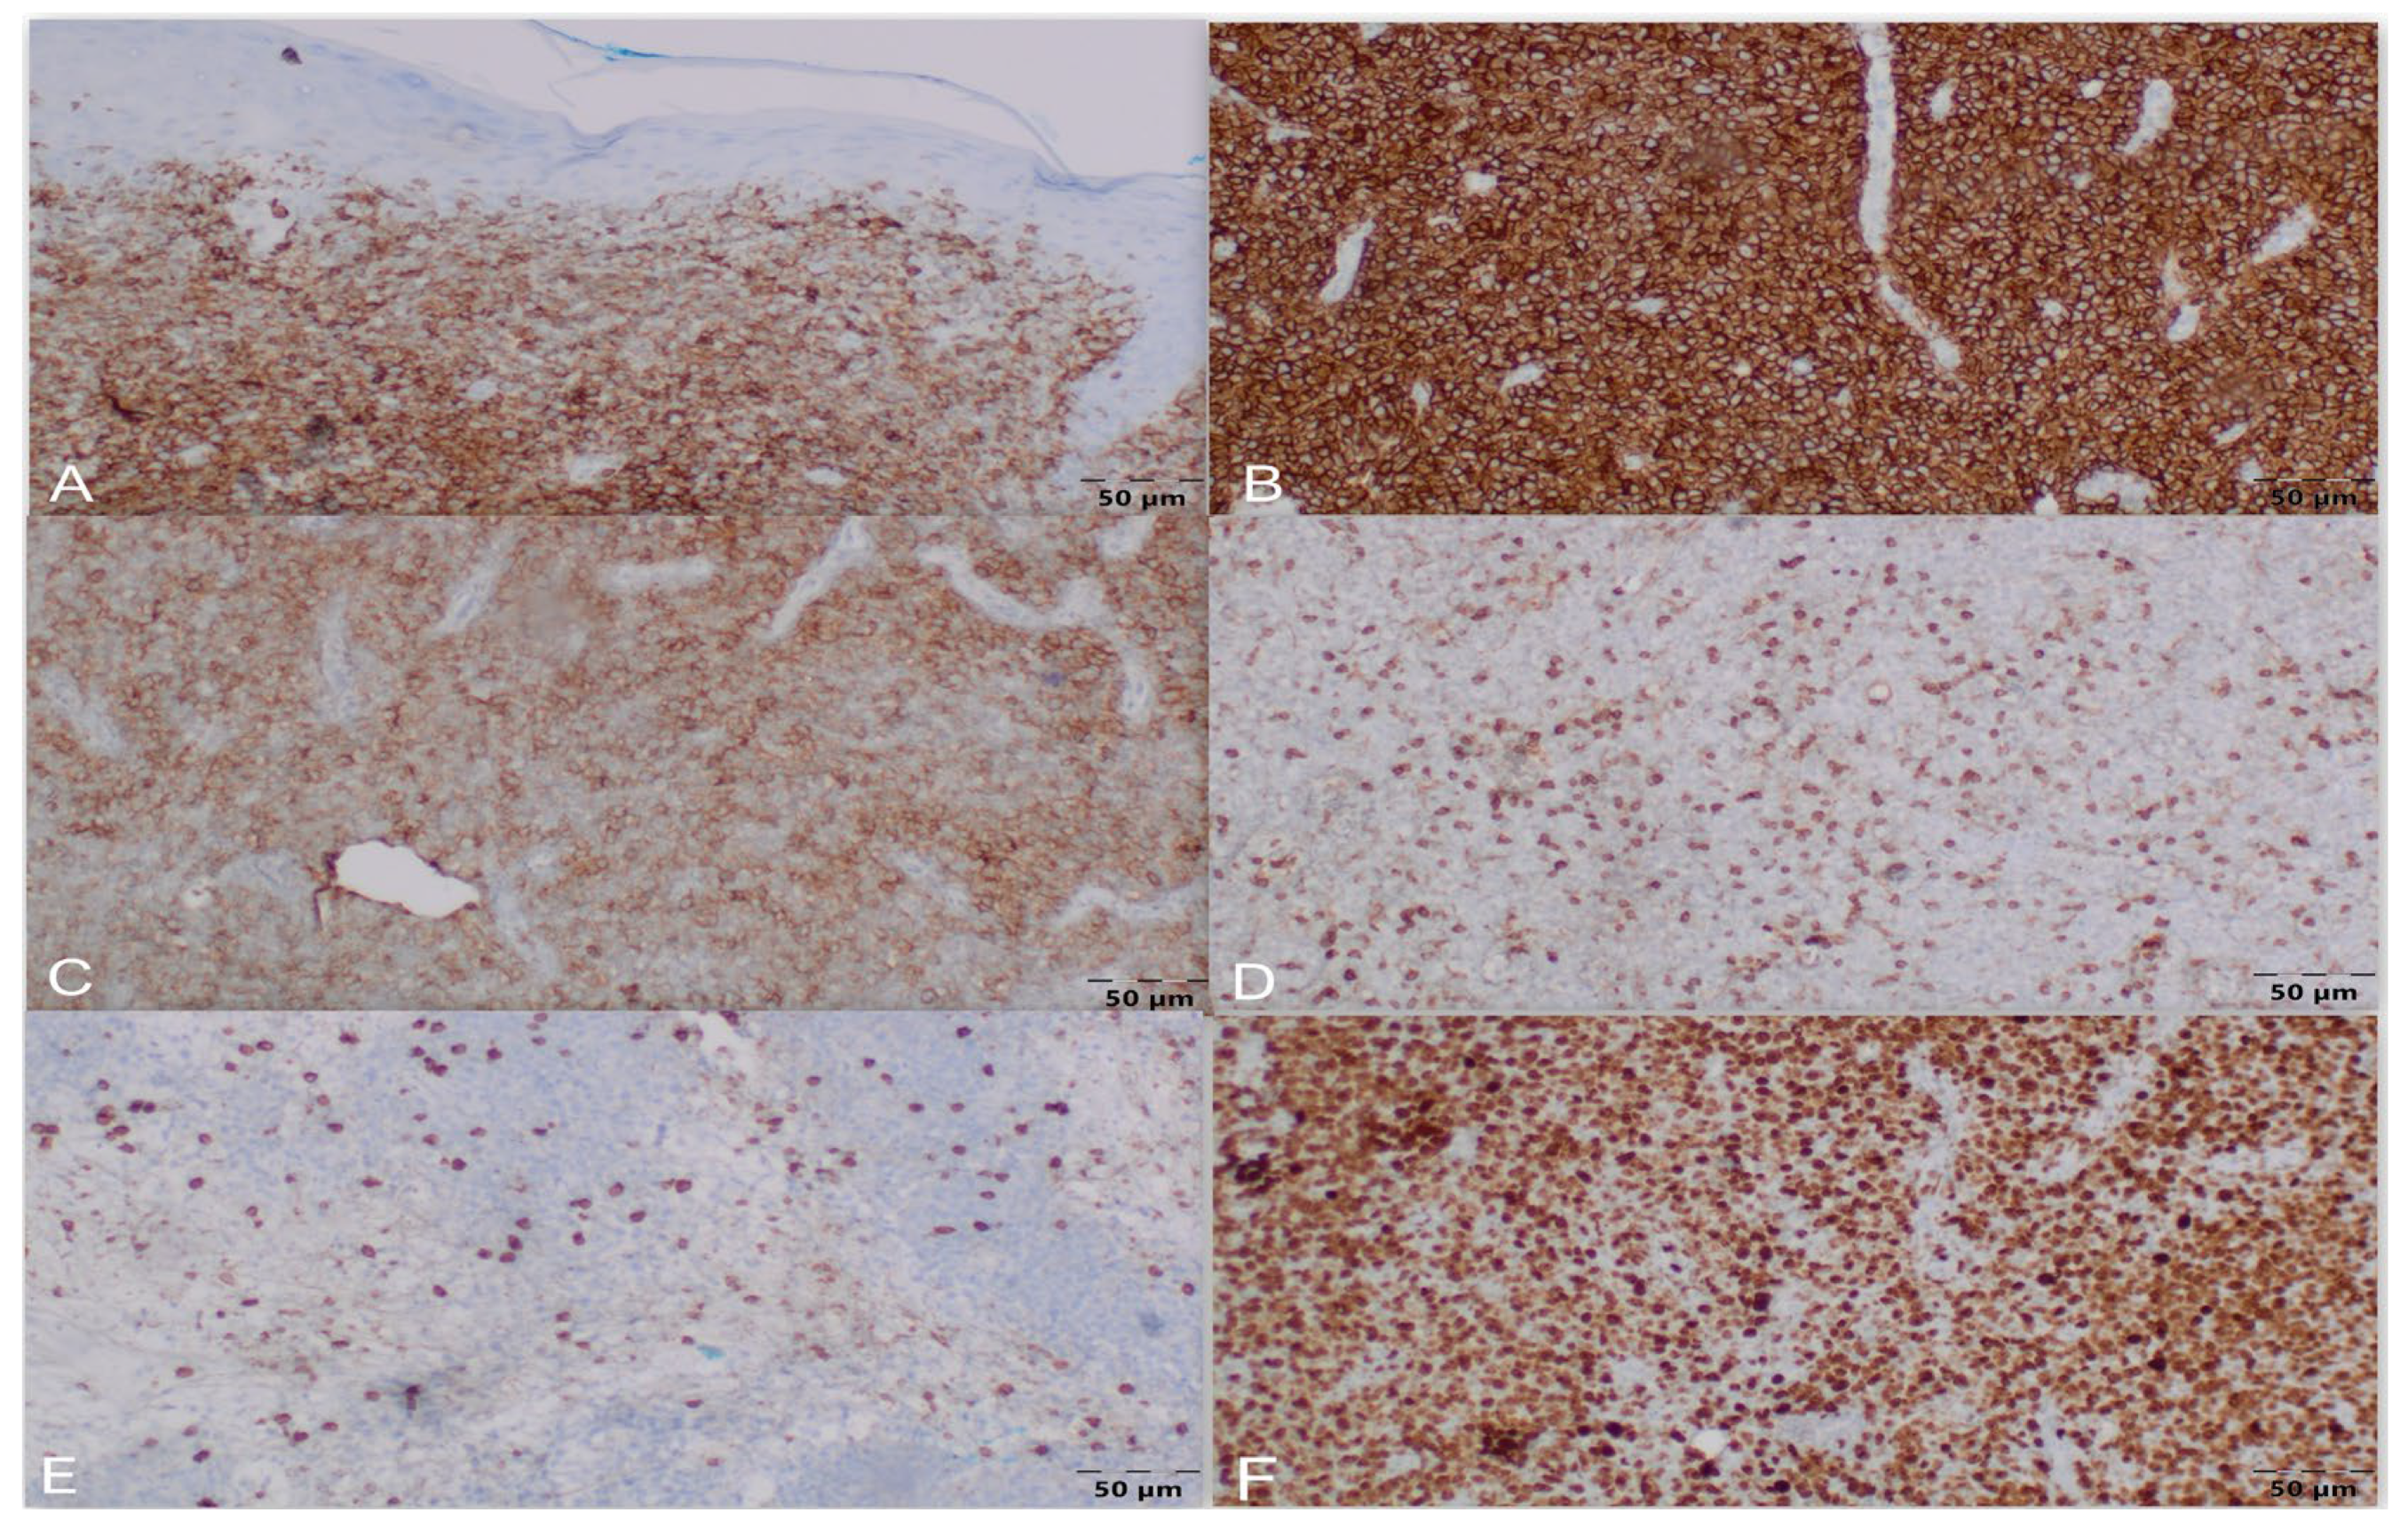

2. Case Presentation